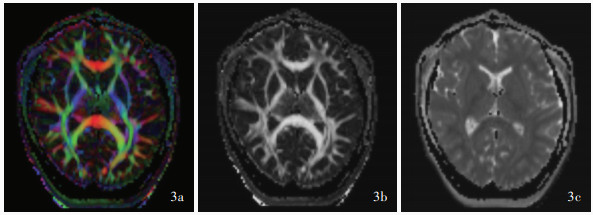

Aoki Y , Inokuchi R , Gunshin M , Yahagi N , Suwa H . Diffusion tensor imaging studies of mild traumatic brain injury: a meta-analysis. J Neurol Neurosurg Psychiatry, 2012, 83: 870- 876.

Hulkower MB , Poliak DB , Rosenbaum SB , Zimmerman ME , Lipton ML . A decade of DTI in traumatic brain injury: 10 years and 100 articles later. AJNR Am J Neuroradiol, 2013, 34: 2064- 2074.

Grant M , Liu J , Wintermark M , Bagci U , Douglas D . Current state of diffusion-weighted imaging and diffusion tensor imaging for traumatic brain injury prognostication. Neuroimaging Clin N Am, 2023, 33: 279- 297.

Wilde EA , Ramos MA , Yallampalli R , Bigler ED , McCauley SR , Chu Z , Wu TC , Hanten G , Scheibel RS , Li X , Vásquez AC , Hunter JV , Levin HS . Diffusion tensor imaging of the cingulum bundle in children after traumatic brain injury. Dev Neuropsychol, 2010, 35: 333- 351.

Arfanakis K , Haughton VM , Carew JD , Rogers BP , Dempsey RJ , Meyerand ME . Diffusion tensor MR imaging in diffuse axonal injury. AJNR Am J Neuroradiol, 2002, 23: 794- 802.

Wallace EJ , Mathias JL , Ward L . Diffusion tensor imaging changes following mild, moderate and severe adult traumatic brain injury: a meta-analysis. Brain Imaging Behav, 2018, 12: 1607- 1621.

Hagmann P , Jonasson L , Maeder P , Thiran JP , Wedeen VJ , Meuli R . Understanding diffusion MR imaging techniques: from scalar diffusion-weighted imaging to diffusion tensor imaging and beyond. Radiographics, 2006, 26 Suppl 1: S205- S223.